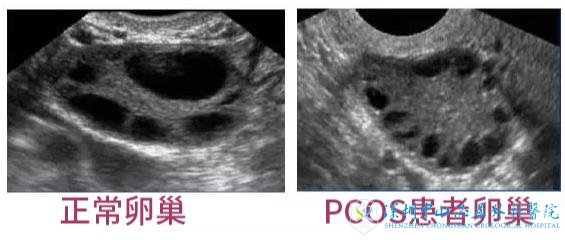

超促排卵需注意:PCOS容易引发无排卵

PCOS女性不孕的根本原因是少排卵或无排卵。事实上,多囊患者会出现稀发月经或闭经等。然而缺乏排卵并不是导致不孕的主要原因,比如肥胖,较差的卵子和子宫内膜都是不利于怀孕的。就算是获卵成功了也会担心卵子的质量问题导致胚胎质量较差,因此,超促排卵期间需严格遵医嘱进行用药。